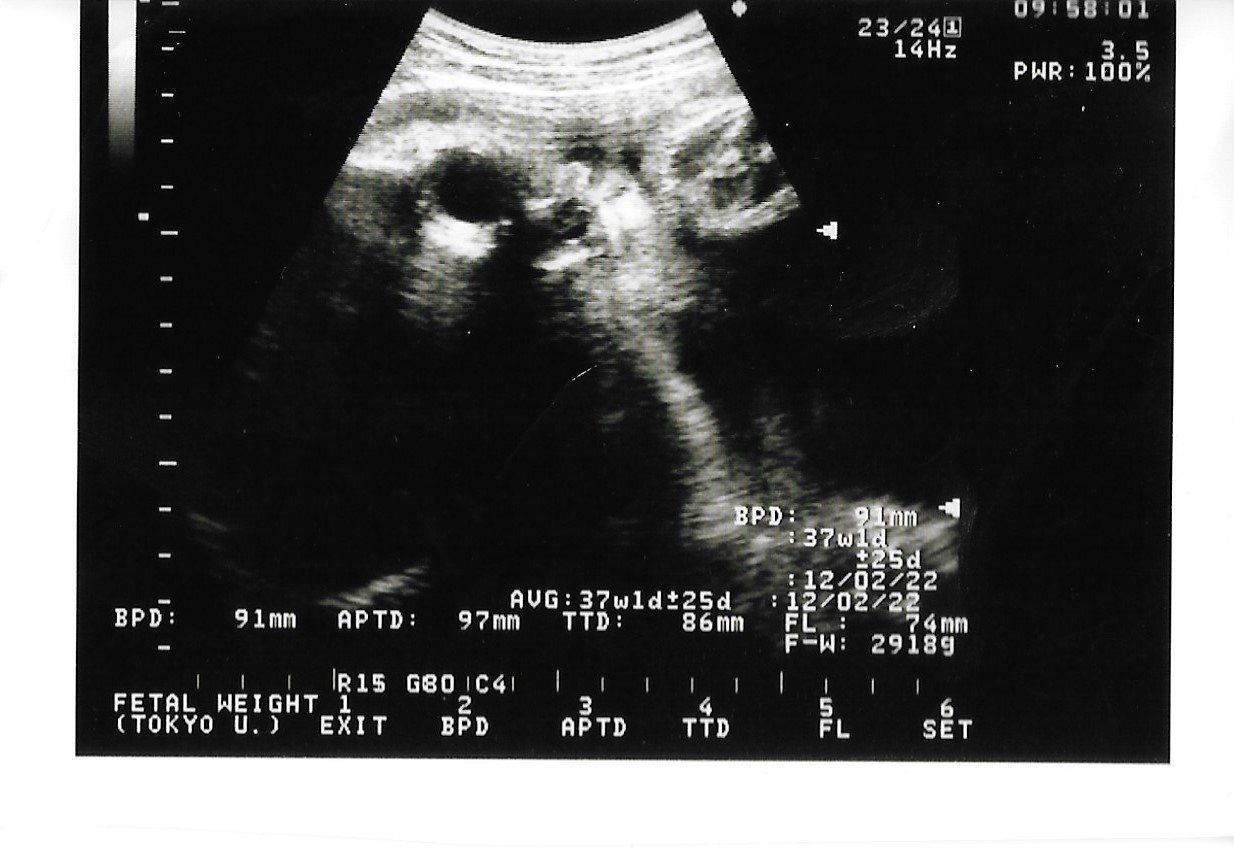

妊娠38週のエコー写真 間もなく生まれる

推定体重2918g。妊娠36週を迎えてからは、検診が週1回になり、おなかにセンサーを貼って胎児の心拍を調べるNST検査が行われます。この日は確か「少しおなかの張っているタイミングがありますね~」と言われました。そして、この日の4日後に出産となるのでした。